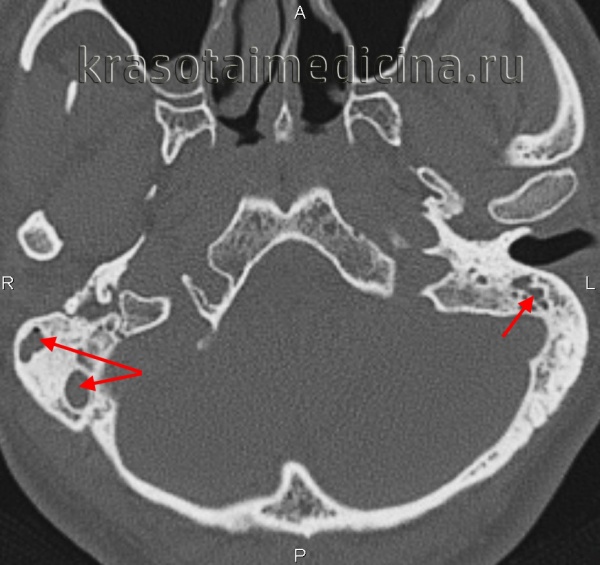

КТ височных костей. Тотальное снижение пневматизации ячеек сосцевидного отростка с обеих сторон. (фото Вишняков В.Н.)

• К рентгенологическим признакам, выявляемым на снимках в проекции Шюллера и на КТ височной кости, относятся снижение рентгенопрозрачности из-за уменьшения содержания воздуха в дыхательной системе, матовое затемнение сосцевидных ячеек, нечеткое изображение тонкой структуры кости в результате декальцификации и разжижения костных септ между сосцевидными ячейками, деструкция кости с очагами разжижения и эрозии соседних структур.

- Рентгенография височной кости. В экссудативной стадии мастоидита обнаруживает завуалированные в результате воспаления ячейки и нечетко различимые перегородки между ними. Рентгенологическая картина пролиферативно-альтеративной стадии мастоидита характеризуется отсутствием ячеистой структуры сосцевидного отростка, вместо которой определяется одна или несколько больших полостей. Лучшая визуализация достигается при проведении КТ черепа в области височной кости.